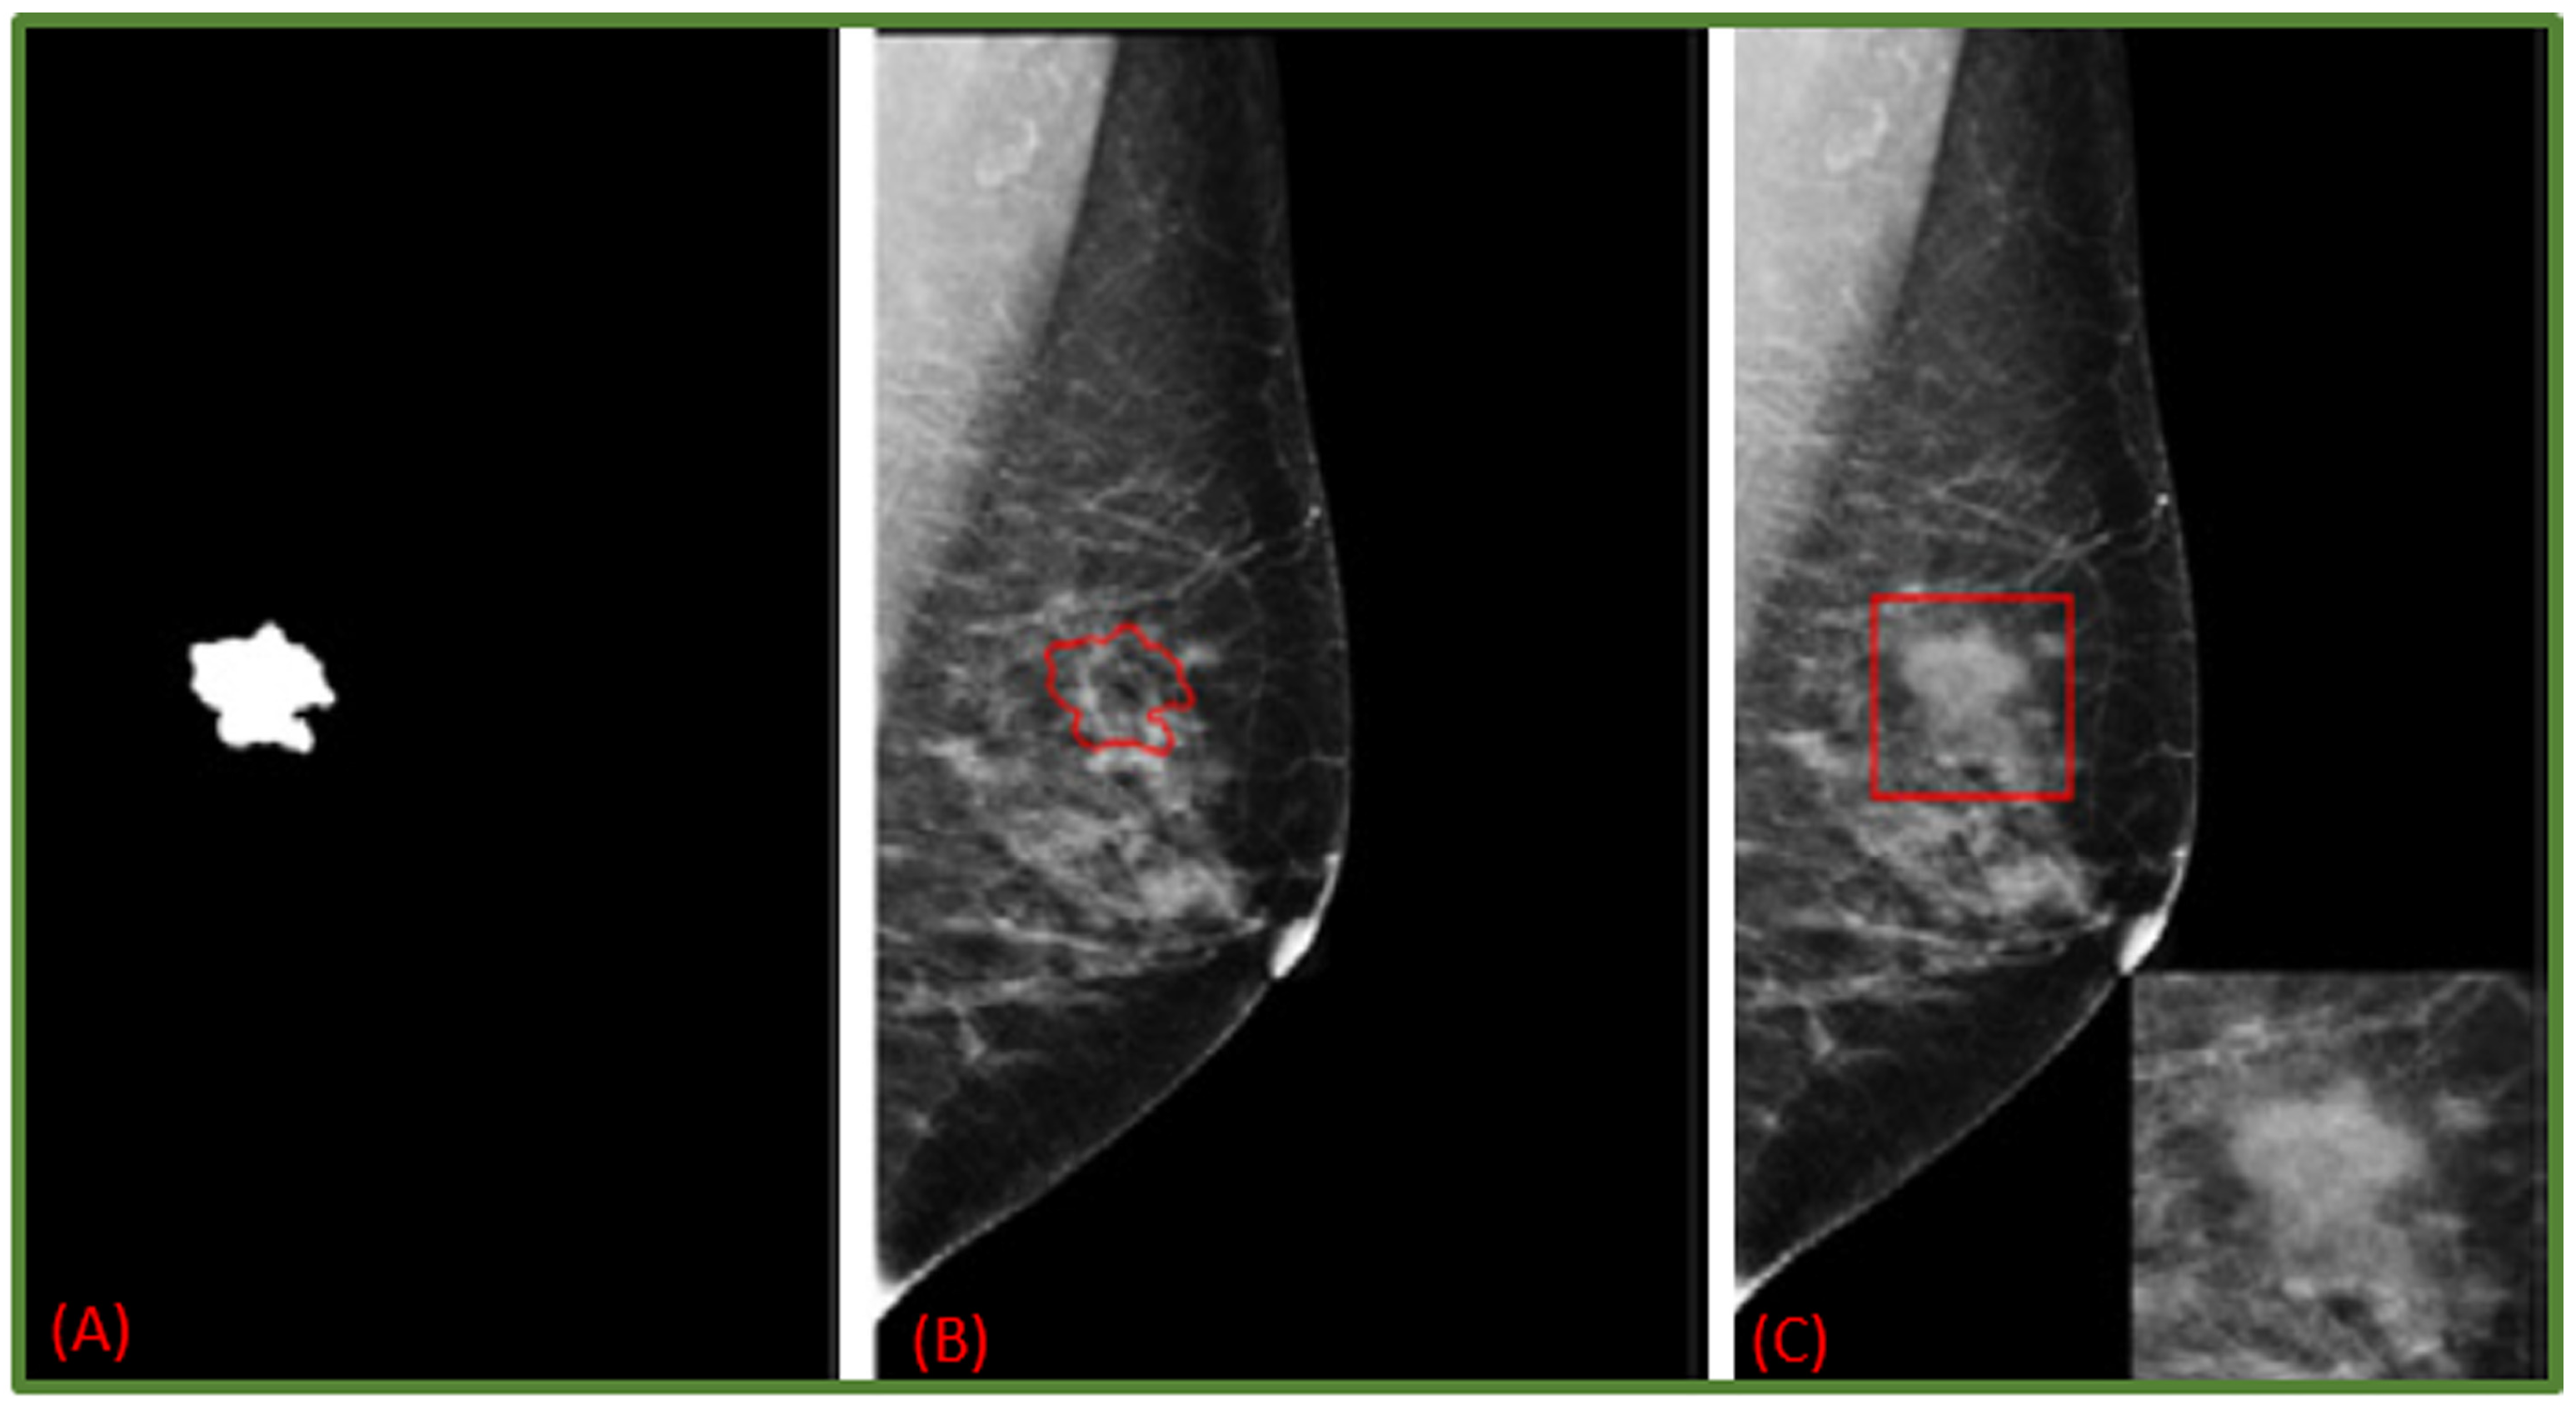

- Costa, A.C.; Oliveira, H.C.; Vieira, M.A. Data augmentation: Effect in deep convolutional neural network for the detection of architectural distortion in digital mammography. In Proceedings of the Brazilian Congress on Medical Physics, Santos, Brazil, 21–24 August 2019. [Google Scholar]

- Cha, K.H.; Petrick, N.A.; Pezeshk, A.X.; Graff, C.G.; Sharma, D.; Badal, A.; Sahiner, B. Evaluation of data augmentation via synthetic images for improved breast mass detection on mammograms using deep learning. J. Med. Imaging 2019, 7, 012703. [Google Scholar] [CrossRef] [PubMed]

- Shen, T.; Hao, K.; Gou, C.; Wang, F.Y. Mass Image Synthesis in Mammogram with Contextual Information Based on GANs. Comput. Methods Programs Biomed. 2021, 202, 106019. [Google Scholar] [CrossRef]

- Zeiser, F.A.; da Costa, C.A.; Zonta, T.; Marques, N.; Roehe, A.V.; Moreno, M.; da Rosa Righi, R. Segmentation of masses on mammograms using data augmentation and deep learning. J. Digit. Imaging 2020, 33, 858–868. [Google Scholar] [CrossRef] [PubMed]